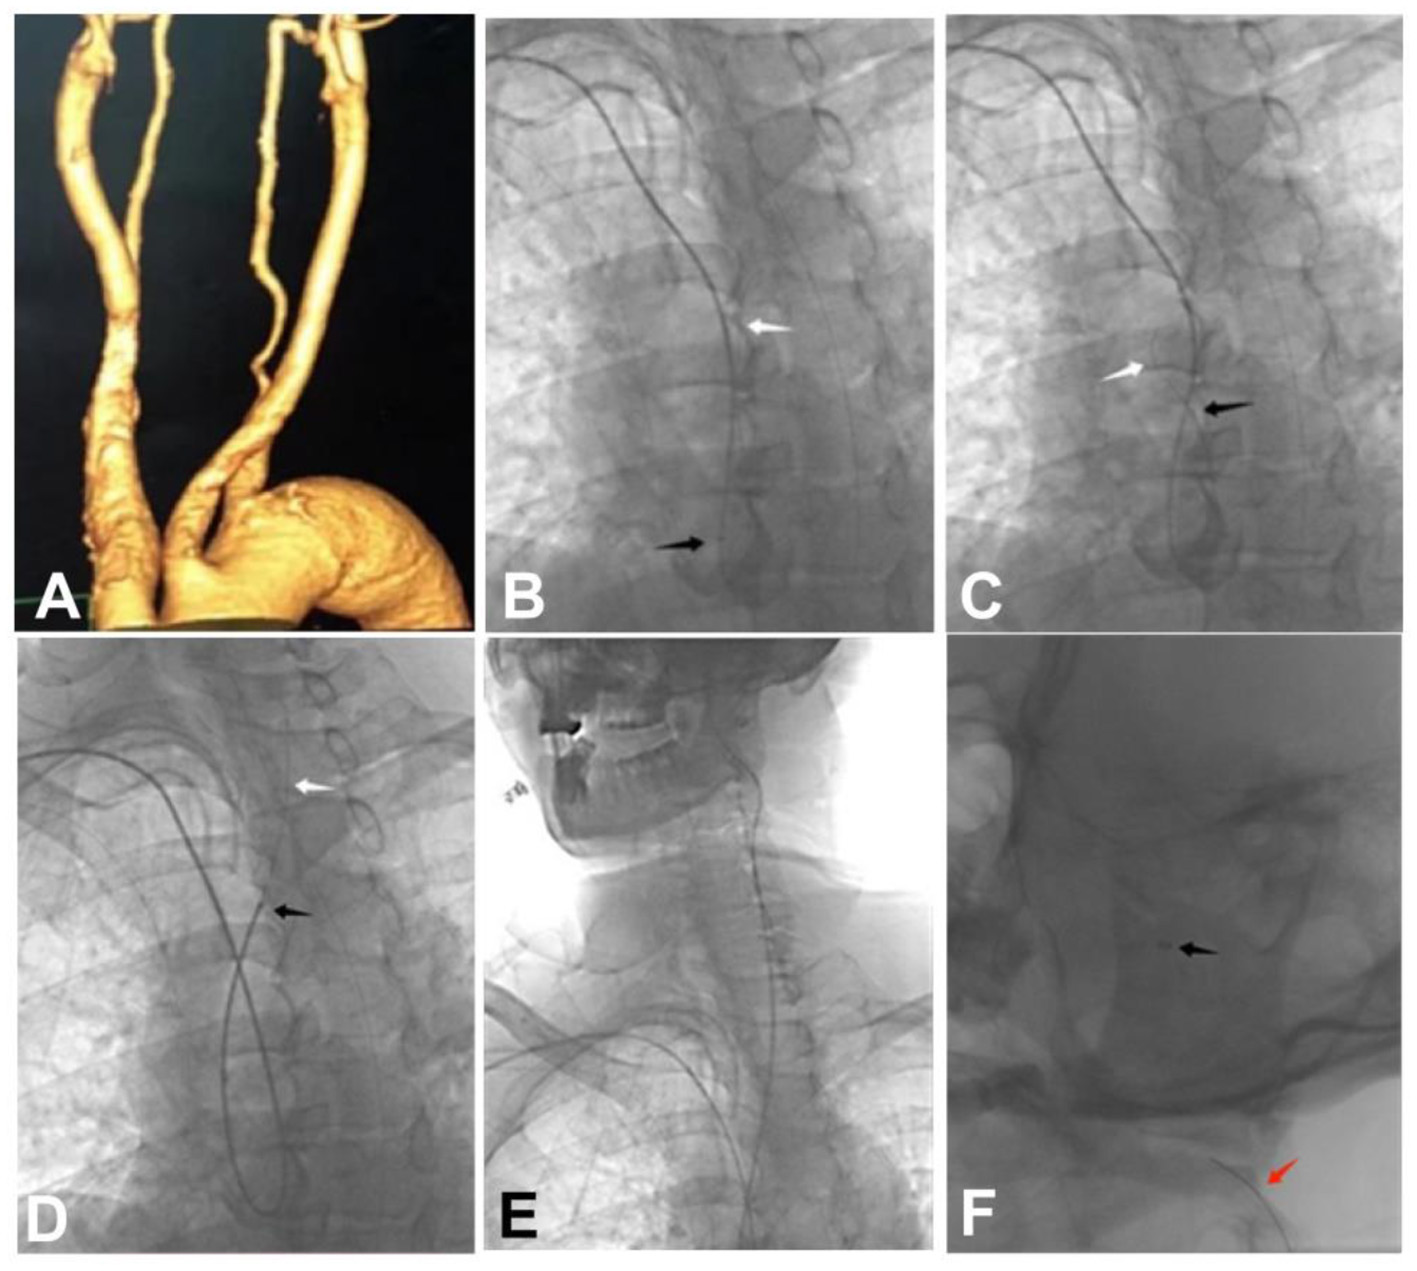

Figure 1

A 59-year-old patient with a left middle cerebral artery aneurysm and a left anterior cerebral artery A2 aneurysm was treated endovascularly through the right transradial access with intra-aortic catheter looping because of the difficulty of embolization via the transfemoral access. (A) Three-dimensional reconstruction angiography revealed a type III aortic arch with widened aortic arch. (B) A 6F115 cm Navien intermediate catheter was guided by a guide wire to form a loop within the aortic lumen. (C) The Navien intermediate catheter was slowly introduced by the guide wire to form a loop within the aorta. (D) The guide wire and the Navien intermediate catheter were used to superselect the left common carotid artery. (E, F) The tip of the Navien intermediate catheter was used to superselect the internal carotid artery, and after the catheter tip was placed at the C2 segment, a V18 guide wire was sent into the Navien intermediate catheter. Black arrow: the tip of the Navien intermediate catheter; White arrow: the guide wire; Red arrow: the V18 guide wire.